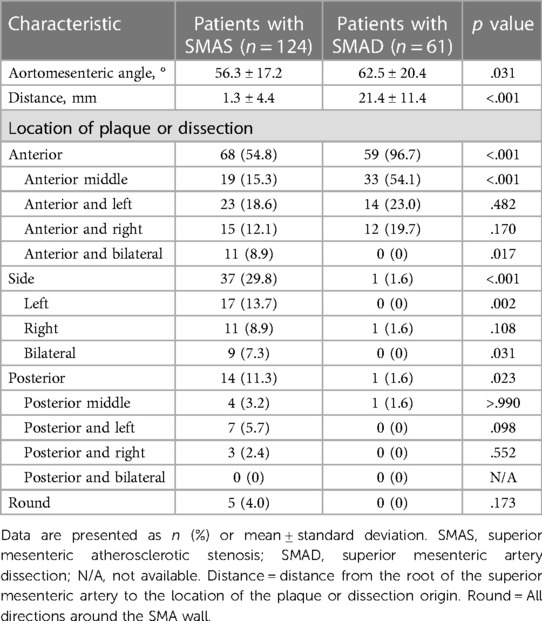

The 3D surface of the SMA was abstracted from the CTA data using Mimics Research 19.0 (Materialise HQ, Louvain, Belgium). The models were then modified based on data from 60 patients, with SMAD (n = 30) and SMAS (n = 30), thirty-one SMAD patients who lack thin-slice CTA data or have poor image quality were excluded in the CFD analysis. At the same time, thirty SMAS patients meeting the including criteria were randomly included. For each model, dissections or plaques were removed and the main morphology features of the SMA trunk were retained to simulate the hemodynamic conditions in the SMA before the onset of SMAD or SMAS; this procedure was performed using Geomagic Wrap 2017 (Geomagic Studio, Raindrop, Research Triangle Park, NC, USA) and SolidWorks 2017 (Dassault Systemes SE, Paris, France) (Figure 2). The SMA models was divided into three segments: the root, the curved segment, and the distal segment. The root was identified as the region 0 to 5 mm away from the SMA ostium; the curved segment was identified as the region 15 to 30 mm away from the ostium; and the distal segment was identified as the region 40 to 55 cm away from the ostium.

Figure 2. The schematic diagram of the progress of removing the plaques and dissections from the models. (A,B) CTA image of plaques at the root of the superior mesenteric artery (SMA) and dissection at the curved segment of the SMA. (A1,B1) The superior mesenteric atherosclerotic stenosis (SMAS) and superior mesenteric artery dissection (SMAD) models before repairing. (A2,B2) the SMA models before the onset of SMAS and SMAD.